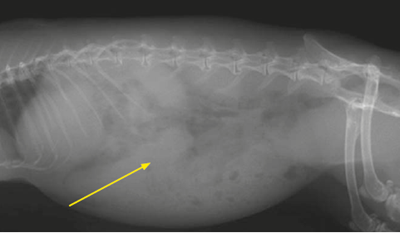

- La radiographie montre une masse abdominale non identifiable.

Elle est caudo-ventrale au foie et ne semble pas en continuité avec celui-ci (Photo 2).

Aucune métastase pulmonaire ou osseuse d’une éventuelle néoplasie n’est mise en évidence.

Photo 2. Radiographie abdominale de profil, une masse homogène est observable dans l’abdomen crânial, cranio-caudalement au foie (flèche). Aucune métastase d’une éventuelle néoplasie n’est observable en région pulmonaire ou sur le squelette.